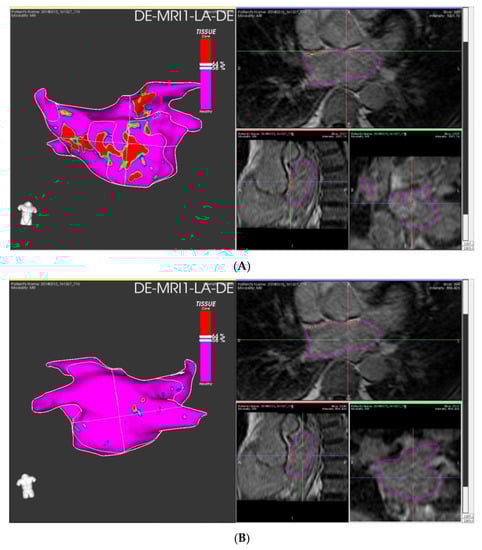

4.2. Procedure Induced Ablation Scars

- Marashly, Q.; Gopinath, C.; Baher, A.; Acharya, M.; Kheirkhahan, M.; Hardisty, B.; Aljuaid, M.; Tawhari, I.; Ibrahim, M.; Morris, A.K.; et al. Late Gadolinium Enhancement Magnetic Resonance Imaging Evaluation of Post– Atrial Fibrillation Ablation Esophageal Thermal Injury across the Spectrum of Severity. J. Am. Heart Assoc. 2021, 10, e018924. [Google Scholar] [CrossRef]

- Chelu, M.G.; Morris, A.K.; Kholmovski, E.G.; King, J.B.; Kaur, G.; Silver, M.A.; Cates, J.E.; Han, F.T.; Marrouche, N.F. Durable Lesion Formation While Avoiding Esophageal Injury during Ablation of Atrial Fibrillation: Lessons Learned from Late Gadolinium MR Imaging. J. Cardiovasc. Electrophysiol. 2018, 29, 385–392. [Google Scholar] [CrossRef]